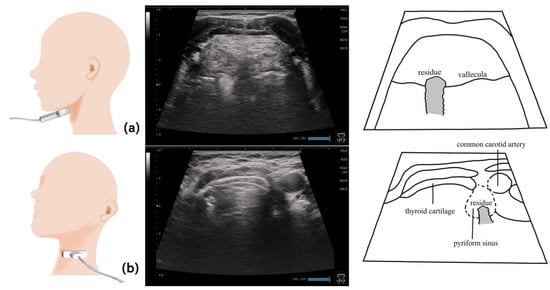

11. Pharynx (Figure 10 and Figure 11)

- Miura, Y.; Yabunaka, K.; Karube, M.; Tsutaoka, T.; Yoshida, M.; Matsumoto, M.; Nakagami, G.; Kamakura, Y.; Sugama, J.; Sanada, H. Establishing a Methodology for Ultrasound Evaluation of Pharyngeal Residue in the Pyriform Sinus and Epiglottic Vallecula. Respir. Care 2020, 65, 304–313. [Google Scholar] [CrossRef]

- Miura, Y.; Nakagami, G.; Yabunaka, K.; Tohara, H.; Hara, K.; Noguchi, H.; Mori, T.; Sanada, H. Detecting pharyngeal post-swallow residue by ultrasound examination: A case series. Med. Ultrason. 2016, 18, 288–293. [Google Scholar] [CrossRef]

- Miura, Y.; Nakagami, G.; Yabunaka, K.; Tohara, H.; Murayama, R.; Noguchi, H.; Mori, T.; Sanada, H. Method for detection of aspiration based on B-mode video ultrasonography. Radiol. Phys. Technol. 2014, 7, 290–295. [Google Scholar] [CrossRef]